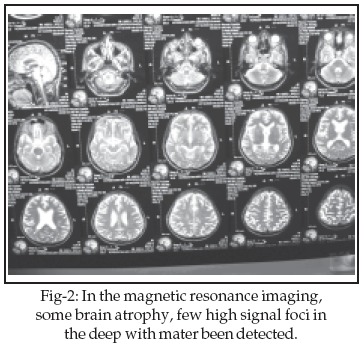

Although neurological symptoms in brucellosis are frequent, central nervous system (CNS) involvement is uncommon. A 42-year-old man was admitted with an episode of faint without loss of consciousness, right hemi paresis, diplopia and headache lasting for four days. The neurological examination revealed left hemi paresis. Limitation of gazing in left eye in lateral view was seen (partial paresis of 6th cranial nerve). The results of laboratory examinations show positive Wright and Coombs Wright in blood and C.S.F. In the brain CT scan hydrocephaly and in magnetic resonance imaging (MRI) some brain atrophy, few high signal foci in the deep with mater had been detected. Treatment included concurrent administration of three drugs: doxycycline, rifampicin and co-trimoxazole. This patient fully recovered.

In the primary brain CT no lesion was seen but some days later hydrocephaly has been detected. In brain magnetic resonance imaging (MRI), some brain atrophy and few high signal foci in the deep white matters of both brain hemisphere was reported. There was not any S.O.L in the supra and infra tentorial structures.